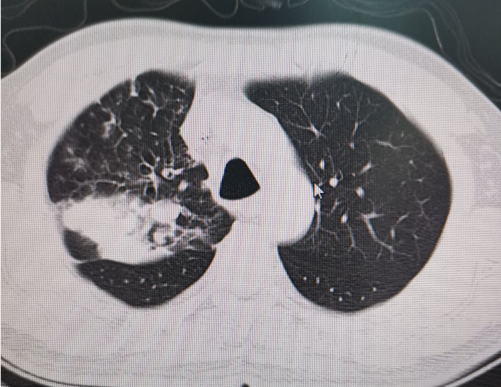

每天来门诊看病的肿瘤患者中,肺癌一般是最多的,当谈及肺癌的严重程度时,有2个关键词不容忽视,大家一定注意,那就是“挺大的”和“中央型”。

“中央型”肺癌则是指肿瘤生长的位置。

中央型肺癌特指起源于段支气管以上气道的恶性肿瘤,其解剖定位涉及肺门核心区(包含主支气管、肺动脉干、上下肺静脉及支气管动静脉)。由于这个位置特殊,中央型肺癌在生长过程中更容易侵犯到这些重要的结构,导致一系列严重的并发症如:声带麻痹、上腔静脉综合征等。